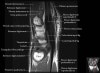

Axial PD fat suppressed evaluates the tendons of the wrist and carpal tunnel, including the median nerve.